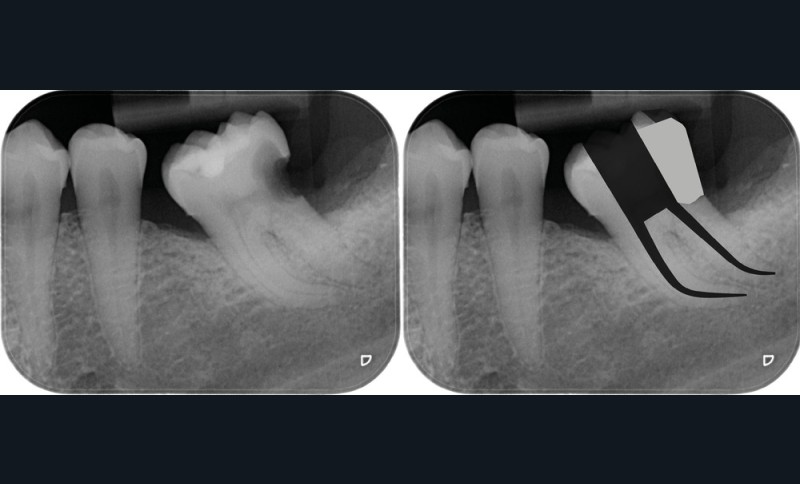

Une cavité d’accès trop petite [2] optimiserait le pronostic biomécanique (préservation dentaire maximale) mais pourrait compromettre le pronostic endodontique : mauvaise lecture de l’anatomie, instrumentation partielle, non ergonomique et avec risque de fracture, défaut de nettoyage des parois canalaires [3], irrigation inadéquate, difficulté d’obturation canalaire, voire d’obturation coronaire. Ce sera le cas des cavités d’accès « Ninja » [4] ou ultraconservatrice (fig. 1), des cavités d’accès « Truss » [5] (fig. 2), des cavités d’accès dites « opportunistes » [6] (fig. 3).

Une cavité d’accès moderne, dictée par l’anatomie et la pathologie de la dent, optimiserait à la fois les pronostics endodontiques et biomécaniques et donc la longévité de la dent sur l’arcade (patient-centered dentistry ou dentisterie centrée sur le patient) (fig. 5).

Il n’existe pas aujourd’hui, dans la littérature de haut niveau, de preuve montrant la supériorité biomécanique d’une cavité d’accès par rapport à l’autre [7]. De plus, la question de la pertinence clinique des cavités d’accès minimalement invasives se pose, notamment en raison du faible nombre d’indications : combien de dents aujourd’hui seront concernées par ces traitements dont la table occlusale est intacte ?